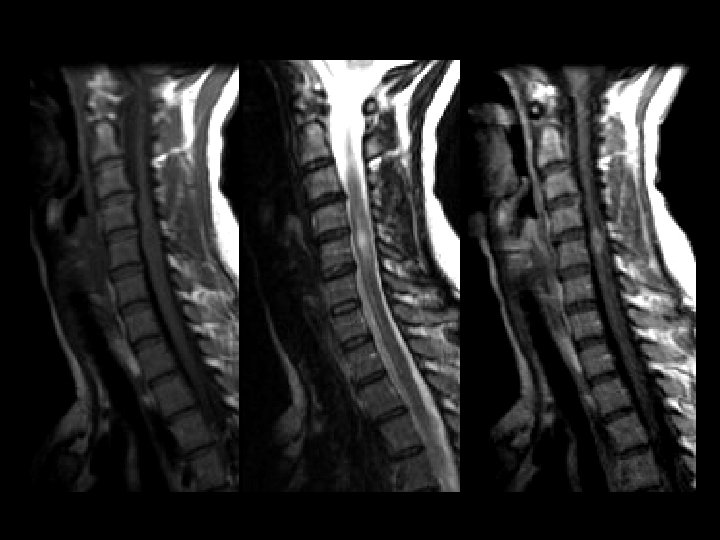

Spinal Sarcoid • Findings: – Iso T 1, hyper T 2, enhancing lesion of cervical spinal cord – No significant cord expansion • Idiopathic system disease characterized by noncaseating granulomas • Young, black women • Image the brain, check CXR • ddx: – Transverse myelitis – Demyelinating dz (MS) – Primary cord tumor (ependymoma, astrocytoma) – Met (uncommon)